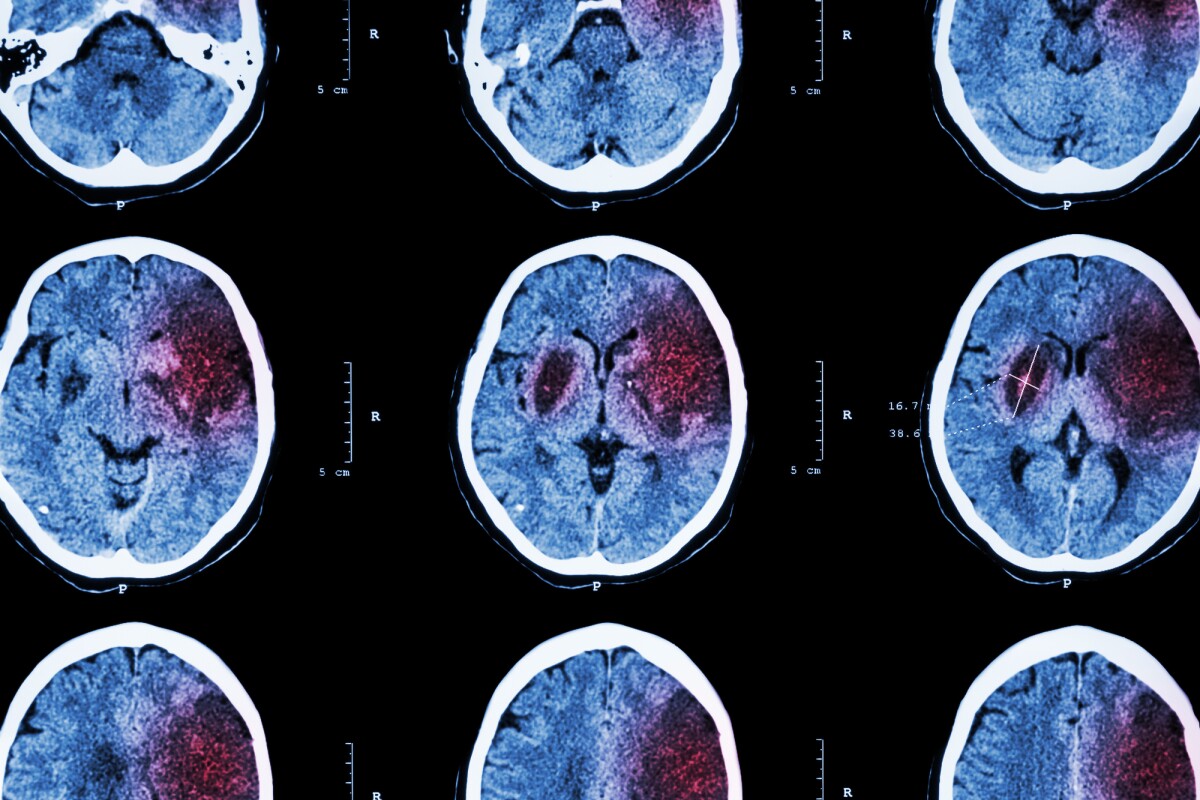

An ischemic stroke occurs when a blood vessel blockage interrupts blood flow to the brain, causing neurons to die off. Survivors can suffer impaired fine motor control and speech, and other disabilities, for which long-term rehabilitation is often required.

But in a new study, researchers at Ohio State University found a promising alternative – a drug known as gabapentin that essentially rewires the undamaged part of the brain to repair broken connections between neurons and restore motor functions.